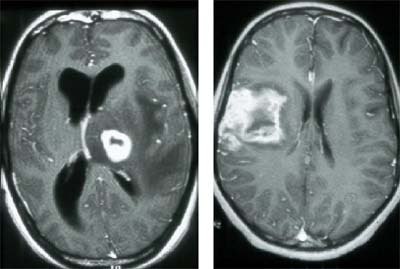

The most common fungal infection in AIDS patients is cryptococcosis, and though this infection can mimic TB meningitis, sometimes the two can be distinguished in imaging. Cryptococcosis tends to spread up the perivascular spaces from the base of the brain, forming small cysts or occasionally masses, which can be seen on CT and MRI. In the lab, it's important to check for cryptococcal organisms with an India ink stain. Treatment is lengthy but often effective, he said.

| Cryptococcal infection of the brain in HIV. Images courtesy of Dr. Peter Corr. |